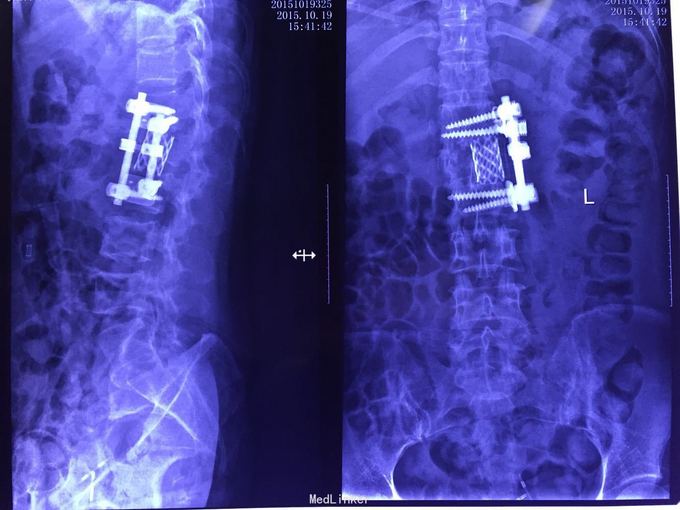

外伤后腰部疼痛伴双下肢感觉运动障碍2月余。 患者马某,女,41岁,2015年8月26日从三楼摔下,当时即出现腰部及下肢的感觉运动障碍,拍片诊断为"1,腰1骨折脱位并神经损伤。2,骨盆骨折,3,双侧肺搓伤并胸腔积液。"并及时对症行手术治疗。

病情稳定后转入我康复医院,现骨盆外固定架已去除,感觉平面右侧自膝关节以下开始减弱,左侧自左踝处开始减弱,二便功能障碍,右下肢髋关节肌群肌力2级,股四头肌,胫前肌等肌力3级,左下肢诸肌群肌力3级。

腰1骨折脱位并神经损伤术后。 前期积极预防并发症,指导床头康复功能锻炼,加强直肠及膀胱管理。针对下肢神经痛,口服加巴喷丁等药物。